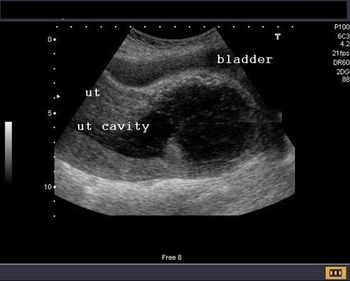

Challenge your diagnostic skills: What is the cause of this young woman’s irregular menses?

What is your diagnosis based on these images from a young woman with irregular menses?